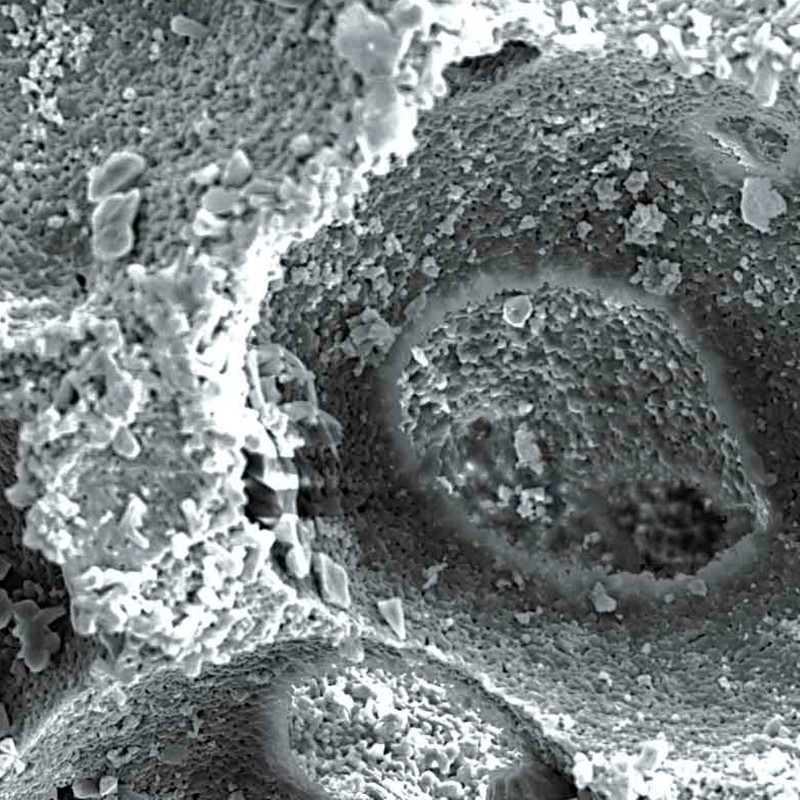

Maxresorb® inject es una pasta ósea sin endurecimiento y lista para el uso compuesta de gel de nano-HA de base acuosa y partículas de Maxresorb®. Debido a su composición específica, las propiedades viscosas de maxresorb® inject permiten una forma, moldeado y ajuste perfectos y una completa adhesión a la superficie ósea circundante del defecto.

Viscosidad y moldabilidad

Debido a su carácter viscoso que no endurece Maxresorb inject se moldea fácilmente en el lugar del defecto. Se adapta a los contornos de la superficie y proporciona el máximo contacto óseo.

Maxresorb® inject es una pasta ósea sin endurecimiento y lista para el uso compuesta de gel de nano-HA de base acuosa y partículas de Maxresorb®. Debido a su composición específica, las propiedades viscosas de maxresorb® inject permiten una forma, moldeado y ajuste perfectos y una completa adhesión a la superficie ósea circundante del defecto.

Viscosidad y moldabilidad

Debido a su carácter viscoso que no endurece Maxresorb inject se moldea fácilmente en el lugar del defecto. Se adapta a los contornos de la superficie y proporciona el máximo contacto óseo.

Biofuncionalidad

Las partículas de nano-HA, ofrecen una superficie muy grande para las interacciones celulares y son rápidamente reabsorbibles.

El componente nano-HA, que representa aproximadamente el 80% del material, se reabsorbe en un plazo de 6-8 semanas.

Los gránulos maxresorb ayudan a mantener el volumen a lo largo del tiempo.

Maxresorb inject es una masilla ósea sin endurecimiento que promueve una rápida regeneración ósea mediante el crecimiento interno de vasos sanguíneos y células a través de su estructura porosa.